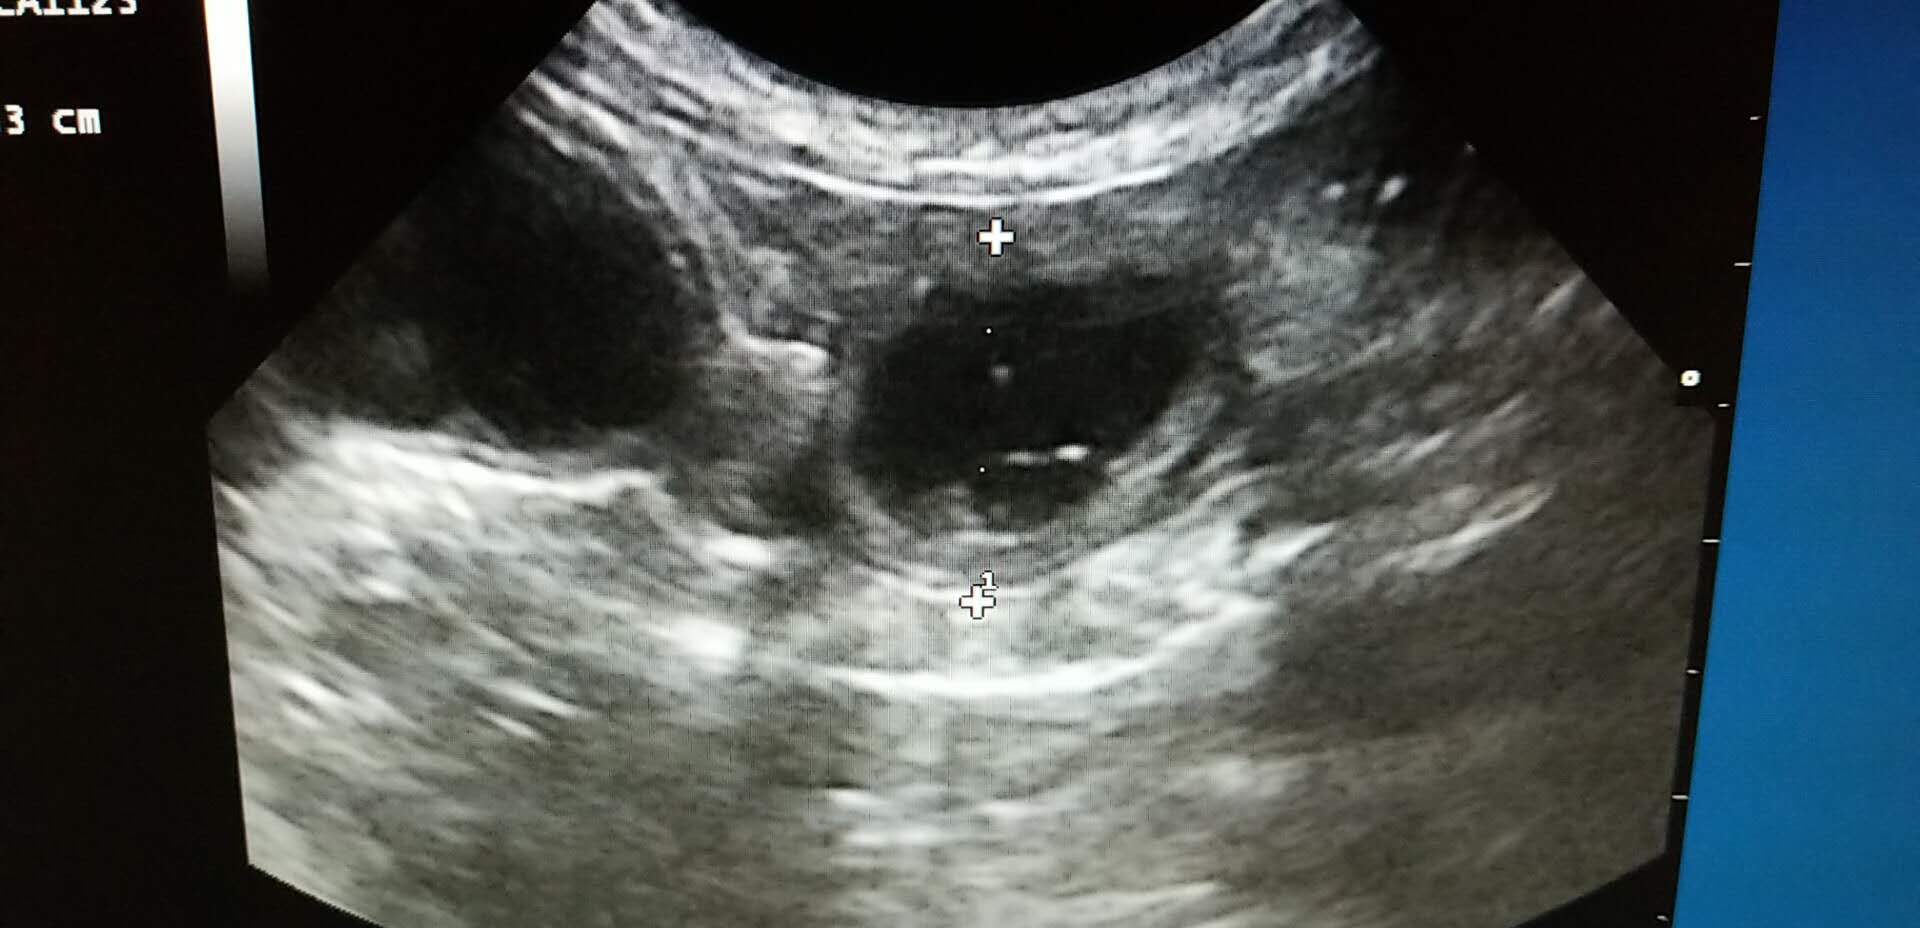

★血液以及影像学检查:血常规提示患猫存在轻度的脱水,生化检查未见明显异常。X-ray提示腹腔存在少量气体,肠腔未见明显异常增大。超声下,可见胃内存在大量的液体,肠腔大量液体,肠道不蠕动,在停止蠕动的肠道段前后扫查,未见明显的异物和肿块。

超声检查

常见是需要排除异物,病毒,淋巴瘤等。功能性肠梗阻的病例,最后需要影像的检查,才能给予更多的信息。排除其他可能的疾病后,如果在超声下发现肠腔积液,前后未见明显异物,并且结合生活史,可以怀疑功能性的肠梗阻。最终的确诊往往需要病理组织切片,这在临床上比较难实现。所以,在临床上,排除一些可能的病因,结合超声影像,即可确诊。